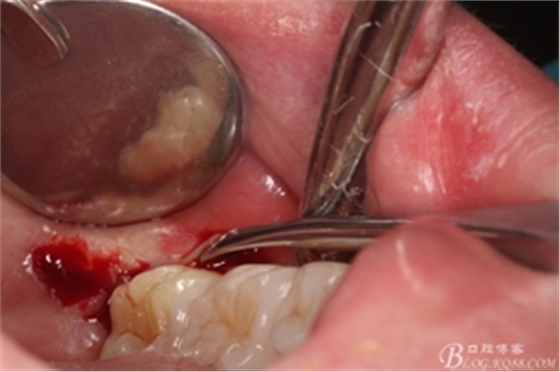

圖8. 翻瓣:建議翻小瓣

圖9.翻開瓣,可見38部分牙冠暴露

圖10. 翻開瓣。38牙冠還有部分骨質(zhì)覆蓋,遂用高速牙鉆去骨